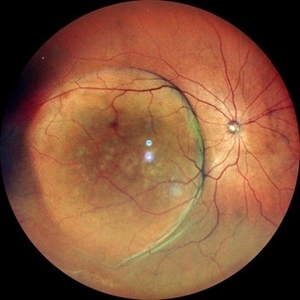

New Choroidal Melanoma with Exudative Detachment

New Choroidal Melanoma with Exudative Detachment

Oct 16 2024 by Virginia Gebhart

56 year old male with a large pigmented tumor with an exudative detachment inferior and shallow fluid through the macula. Pt states they have been having symptoms for over a year. Scheduled for brachytherapy.

Photographer: Virginia Gebhart, Retina Consultants of Carolina

Imaging device: Optos California

Condition/keywords: Choroidal melanoma, exudative detachment, melanoma